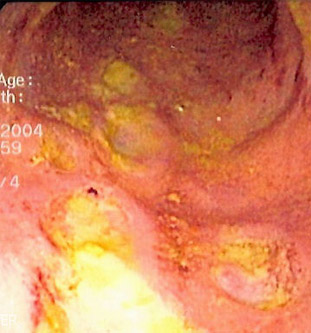

Поражение кожи при болезни крона Кишечник, пораженный болезнью крона